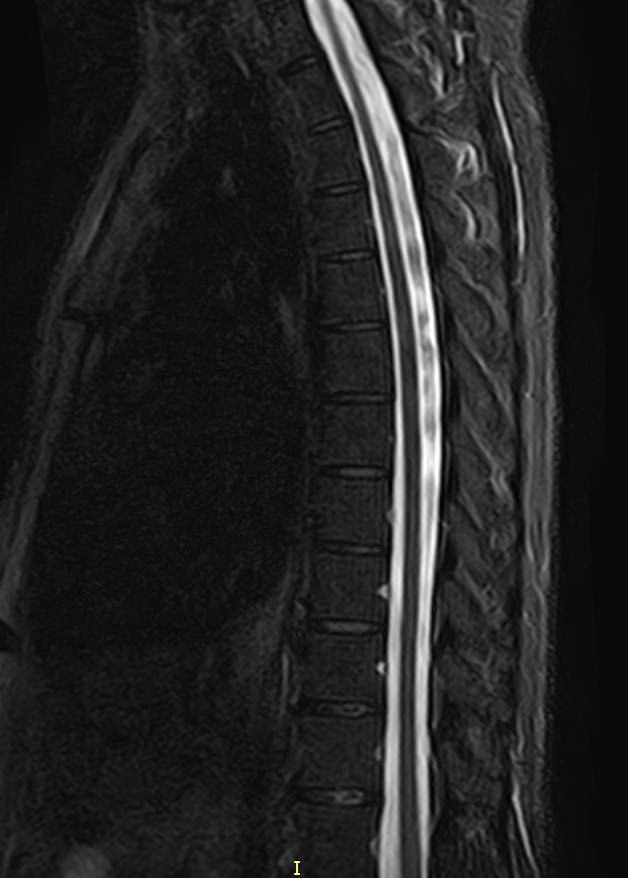

К центральной нервной системе организма относится головной мозг, расположенный в полости черепа, и спинной мозг, проходящий в спинномозговом канале позвоночного столба. В головном мозге находятся высшие центры управления всем организмом, спинной мозг имеет двусторонние связи с ними, то есть является проводником импульсов от периферии к головном мозгу и обратно.

Патология ЦНС может проявляться многообразной неврологической симптоматикой, в зависимости от уровня поражения. Причинами ее появления могут быть травматические повреждения, проникновение инфекции, демиелинизирующие и дегенеративные заболевания, сосудистая патология, опухолевые процессы.

Для диагностики заболеваний ЦНС в клинике «Доступная медицина» проводится комплексное обследование МРТ ЦНС (центральной нервной системы). Клиника укомплектована высокотехнологичным оборудованием, в частности, новейшим 32-канальным высокопольным томографом TOSHIBA VANTAGE TITAN 1,5 Тесла с высокой разрешающей способностью для точной диагностики заболеваний центральной нервной системы.

Комплексное обследование ЦНС выполняется как в стандартном режиме, когда не применяется использование контраста, так и с контрастным усилением. Для более точной диагностики некоторых патологий головного и спинного мозга внутривенно вводится контрастное вещество. С помощью контраста можно обнаружить опухолевые образования размером от 1 мм, демиелинизирующие процессы, дегенеративно-дистрофические заболевания, воспалительные процессы, сосудистую патологию.

МРТ головного и / или спинного мозга показано при диагностике повреждений, структурных отклонений или других состояний, таких как:

• грыжа, повреждение дисков позвоночника;

• планирование операций на позвоночнике, например, такой как декомпрессия сдавленного нерва.